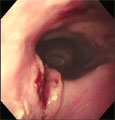

食道造影にて食道拡張が確認された。 内視鏡にて大きな食道内異物を確認した。 バスケット鉗子で部分的摘除。ササミジャーキーだった。 食道内異物完全除去後、やや陳旧性の粘膜裂傷が見つかった。

経過:T:38.8℃、P:120/分、R:60/分。南台動物病院にて食道造影にて食道拡張を認め、異物による食道炎の可能性があると診断されていた。そこで当院にて食道の内視鏡検査を行なった。まず、大きな黄白色の固い異物を確認した。バスケット鉗子で把持したが牽引時に異物の一部が切れてしまった。取り出した異物はササミジャーキーであった。はじめは食道内に残った多量の断片的なジャーキーは内視鏡観察下で大きいものからフィラリア鉗子を用いて一片づつ摘除していた。しかしジャーキー以外の異物はないことを確認したので、小さな断片を噴門前に集めスコープで送気しながら、スコープで胃内に全て押し入れた。食道内異物消失後の精査にて、ジャーキーの角が粘膜に引っかかっていたために生じたと思われる陳旧性の粘膜裂傷を1箇所見つけた。細かい断片処理に時間がかかり処置時間は全部で114分であった。食道粘膜裂傷の影響が心配されたが、次第に食道炎症状は改善し、10日後にはふやかしたフードをよく食べているとのことだった。